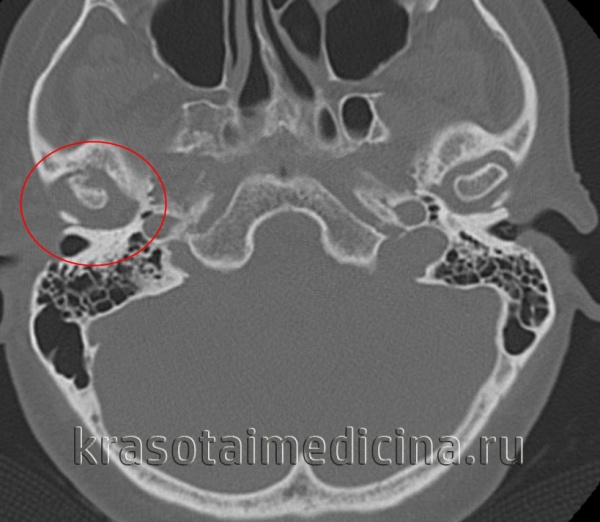

(Слева) На корональной КТ без КУ у этого же пациента определяется выраженное увеличение правого мыщелка, соединенного с височной костью костным мостиком с наружной стороны. Суставное пространство облитерировано. Шейка мыщелка и ветвь нижней челюсти утолщены.

(Справа) На аксиальной КТ без КУ у этого же пациента определяется склероз и увеличение всех размеров мыщелка со слиянием с височной костью. Суставное пространство не визуализируется.